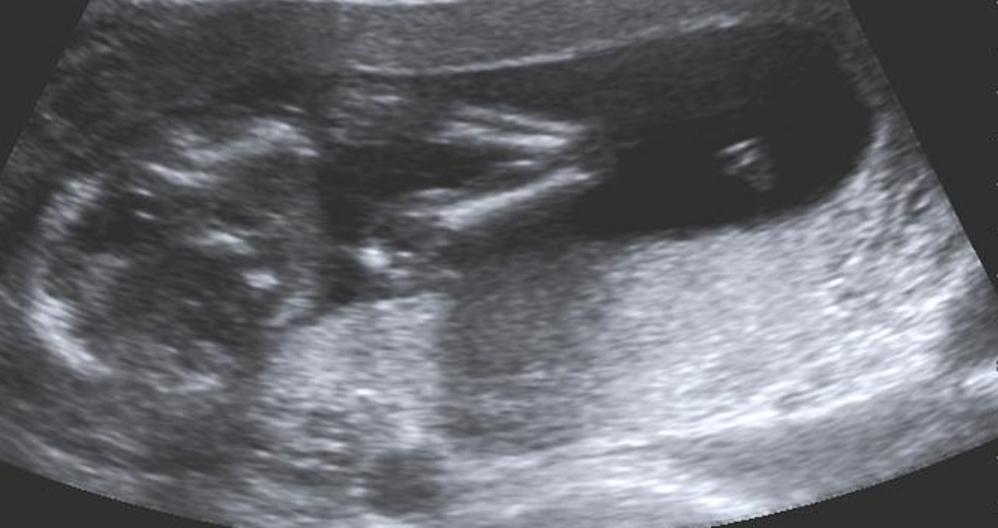

16 week potty shot told boy BabyCenter Boy Potty Shot 14 Weeks What sid the potty shot show and what did the ultrasound tech say you could possibly be having? I have a boy already and was told boy at 15 weeks with him and it was super obvious. This is my potty shot at 14 weeks they wouldn’t tell as if it was a boy or girl as to early! At. Boy Potty Shot 14 Weeks.

Elimination Communication How I Potty Trained Our Newborn Boy Potty Shot 14 Weeks It looks a little like a fork, i've never seen that before in a potty shot. We found out at our 20 weeks scan we having a little boy! At 13 weeks most us techs can tell, but lay people generally cannot. Far from being seen as just a theory, the three lines or 'potty shot' on a scan are. Boy Potty Shot 14 Weeks.

Potty shot pics please! August 2019 Babies Forums What to Expect Boy Potty Shot 14 Weeks We found out at our 20 weeks scan we having a little boy! This is my potty shot at 14 weeks they wouldn’t tell as if it was a boy or girl as to early! At 13 weeks most us techs can tell, but lay people generally cannot. It looks a little like a fork, i've never seen that before. Boy Potty Shot 14 Weeks.